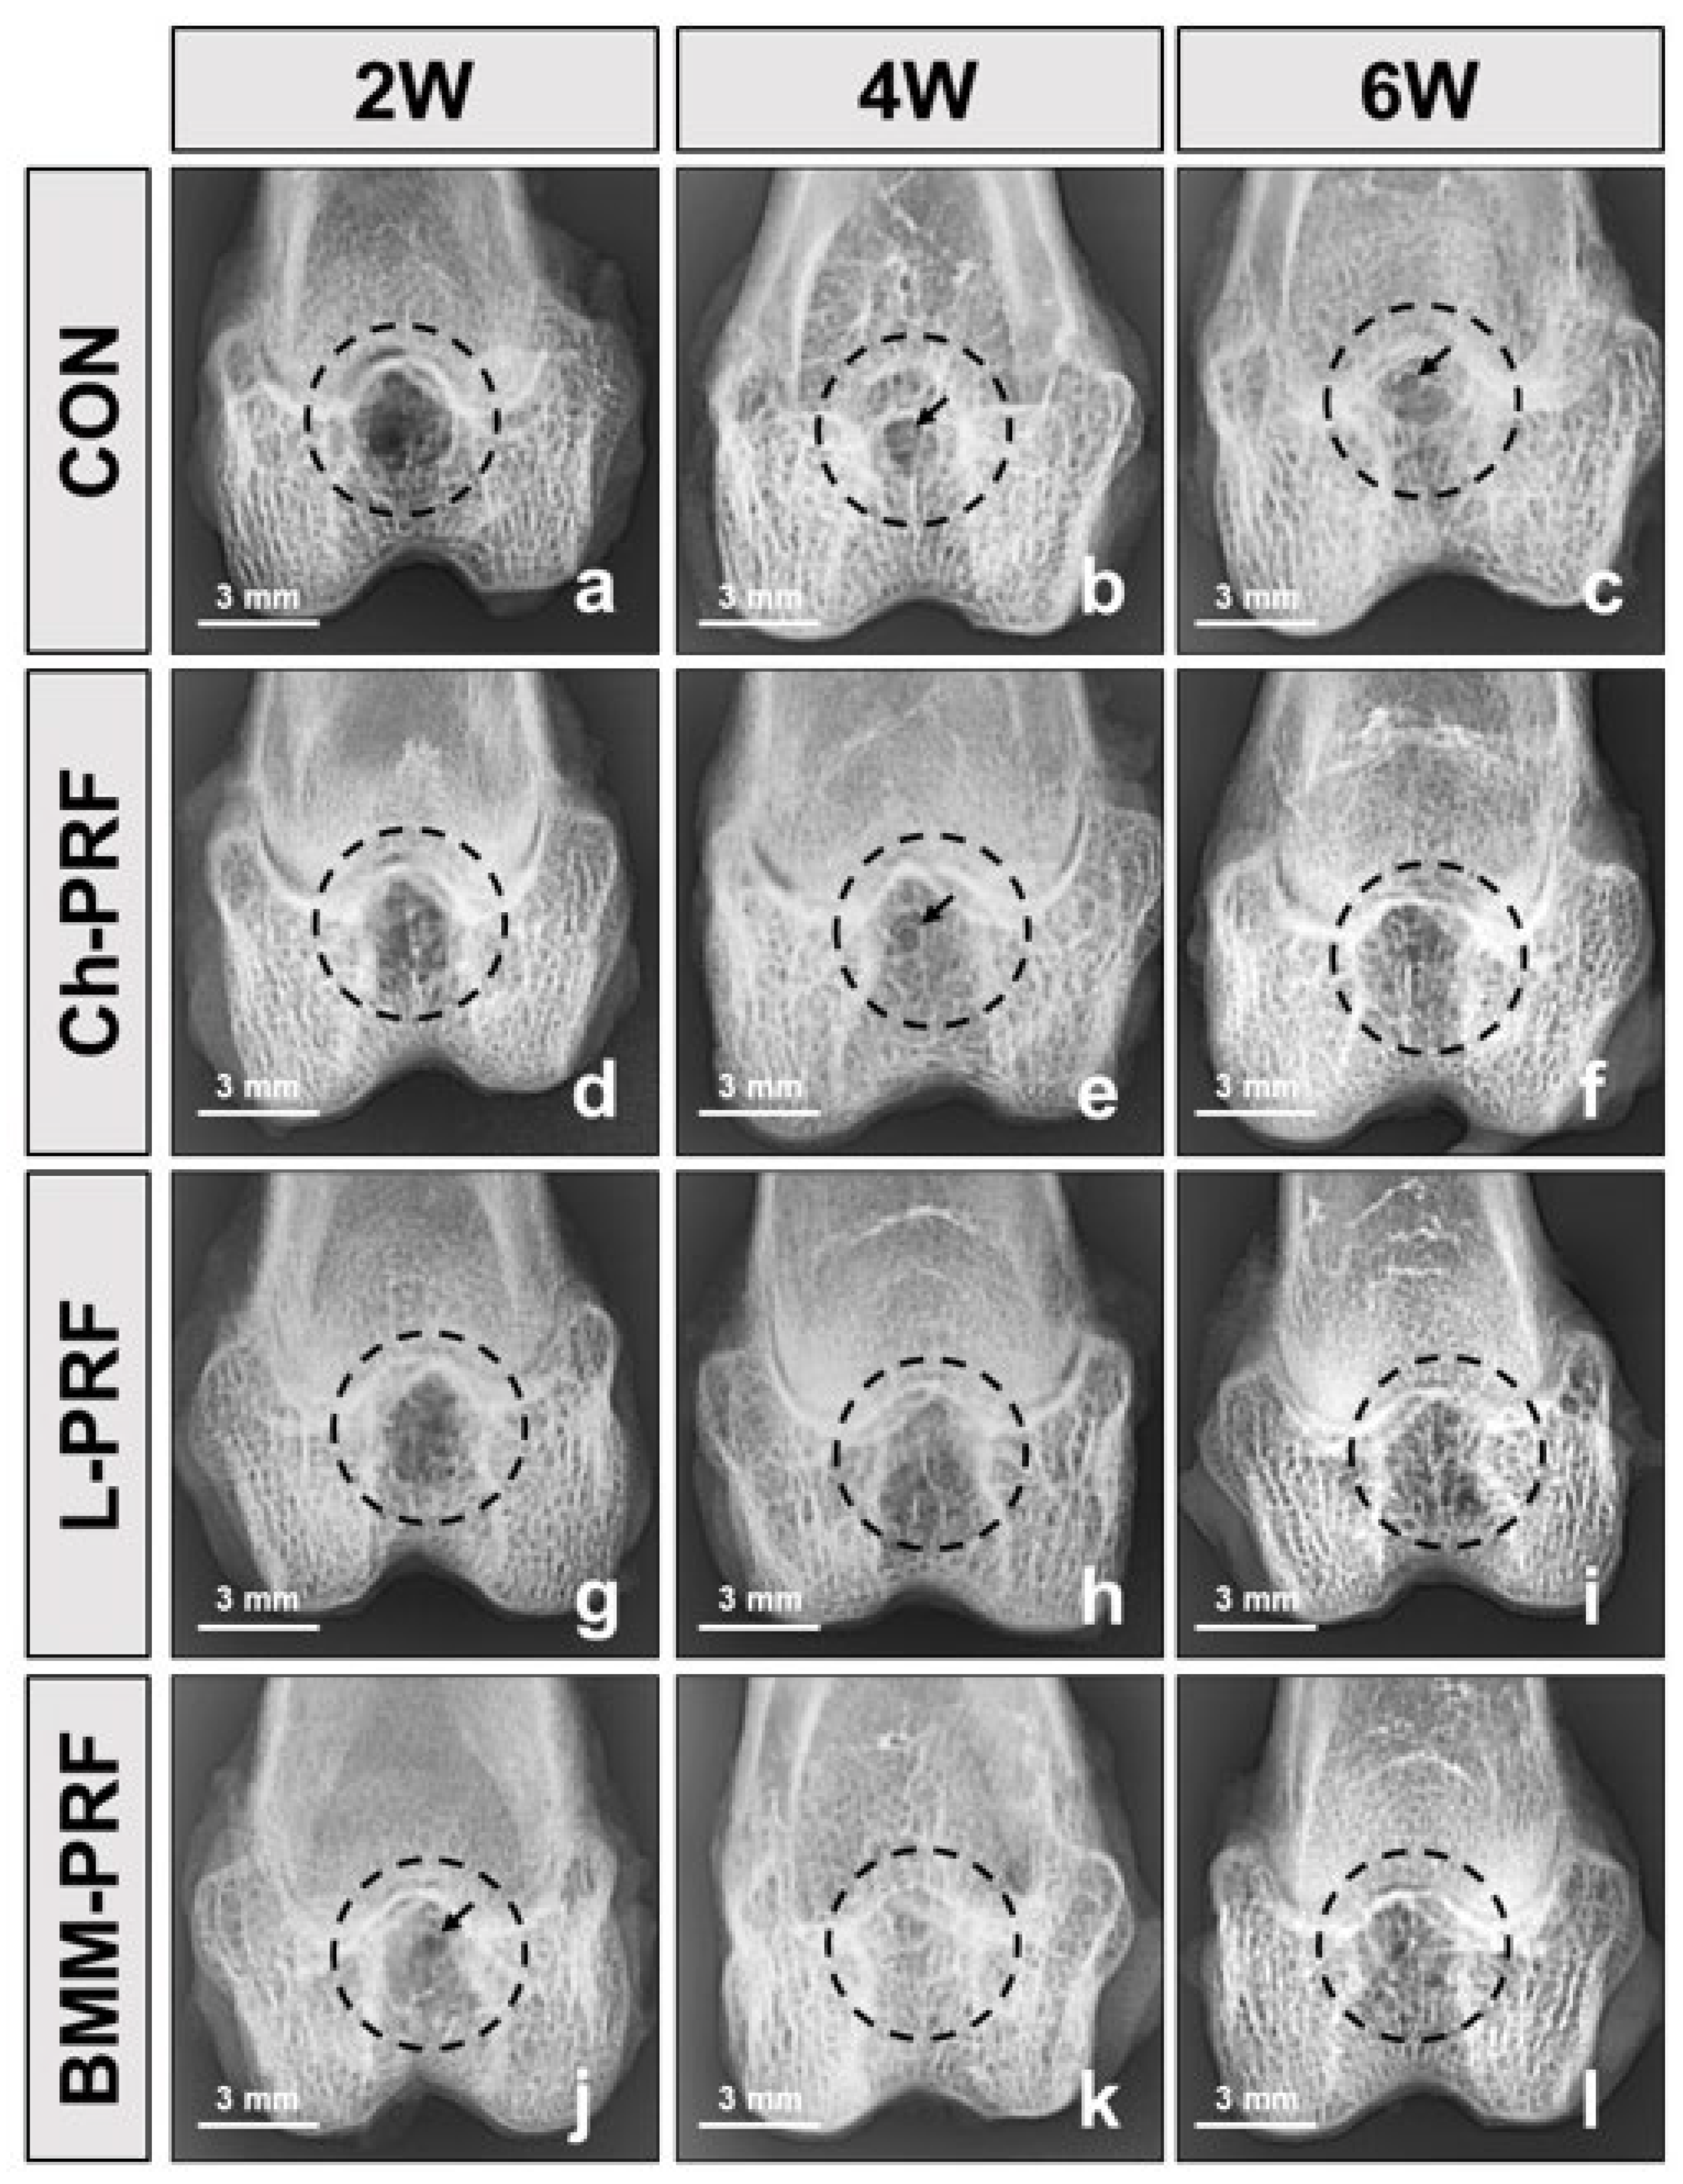

3.3. Macroscopic Assessment of Osteochondral Regeneration

3.4. Microscopic Evaluation of the Osteochondral Regeneration